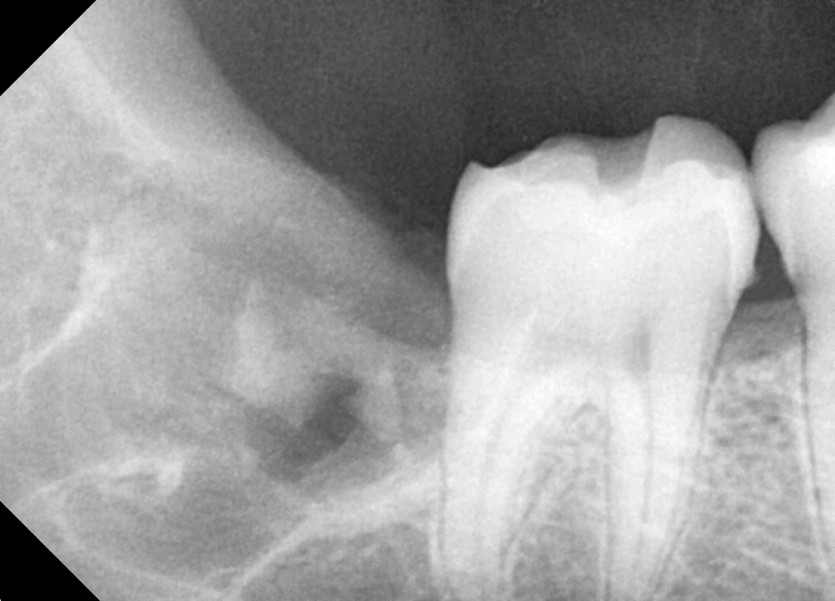

#18,28,38,48 사랑니 발치

구강 외과 전문의가 당일 발치했습니다.